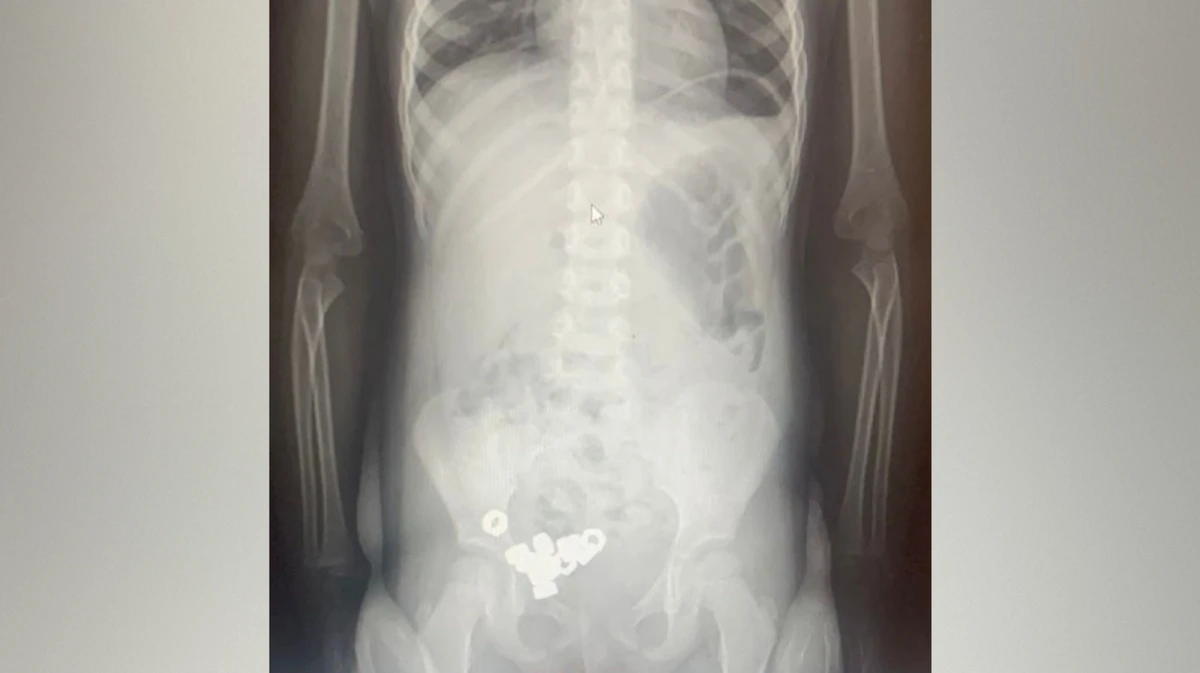

В Воронеже трехлетний малыш проглотил 16 гаек. Ребенок поступил в приемное отделение областной детской клинической больницы №2, жалоб на плохое самочувствие у мальчика не было. Рентген брюшной полости показал в желудке ребенка много маленьких инородных предметов. Из-за высокого риска осложнений малыша госпитализировали. Об этом сообщили в пресс-службе министерства здравоохранения Воронежской области в понедельник, 17 ноября.

Врачи назначили ребенку диету, покой, контроль стула и рентгенографию в динамике. К третьему дню все инородные тела успешно вышли естественным путем, ребенка выписали.